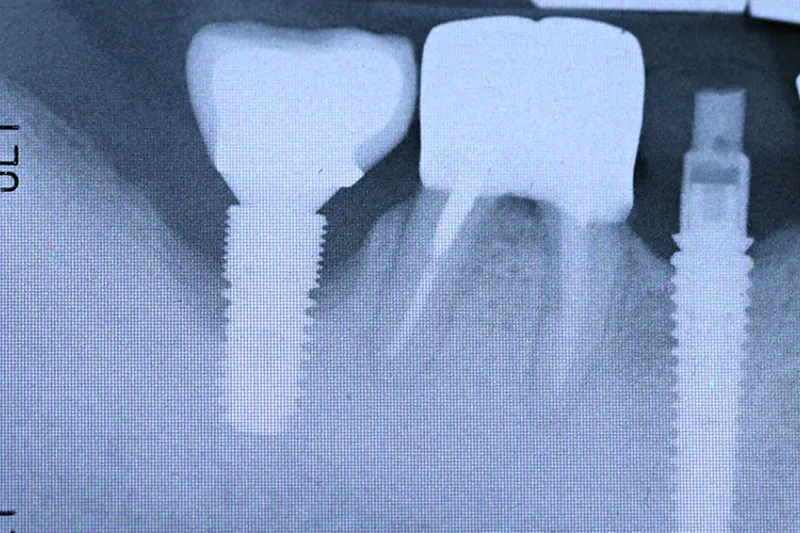

Intraorale optagelser skal tages med parallelteknik, og implantatets gevind skal stå skarpt for at kunne vurdere det marginale knogleniveau samt tilpasningen mellem de forskellige implantatkomponenter. Er gevindet ikke skarpt og veldefineret i begge sider, skal man tage et nyt billede, hvor man med fordel kan anvende huskereglen ”RB-RB/LB-LB”, som fortæller, hvordan vinklingen af tubus skal ændres ved omtagningen.